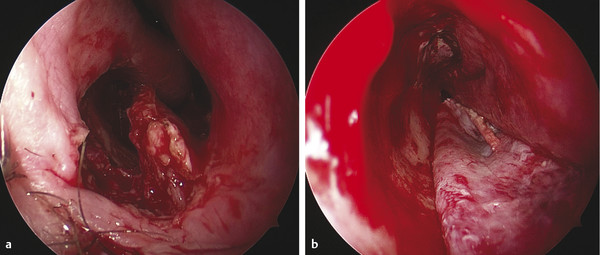

Rim and refresh the septal perforation edges with a knife until obtaining bleeding mucosal margins (Fig. 17‑5).